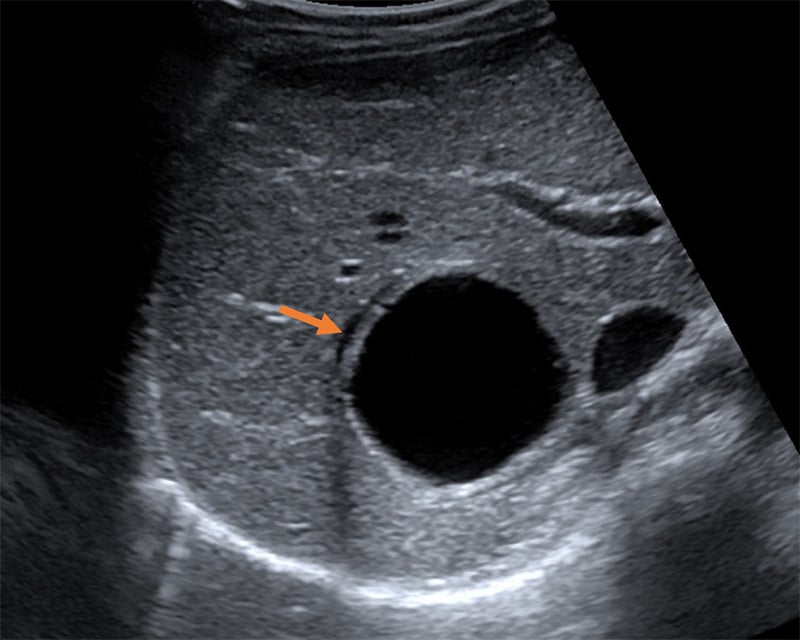

- "Double-wall sign" often seen with high-frequency probe is specific to hydatid cysts and differentiates it from simple cysts.

Figure 41. Type CE1 demonstrating the “double wall sign” distinguishing the lesion from other simple cysts. (Liver Imaging Atlas, www.liveratlas.org. Copyright 2010 University of Washington. Image use with permission from University of Washington, accessed 4/14/21)